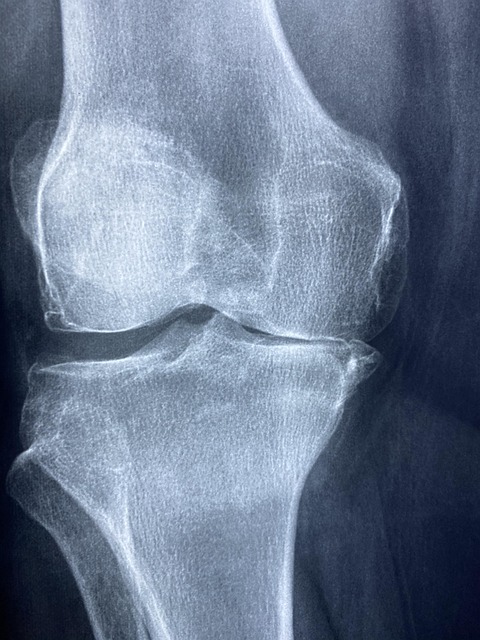

관절이 아프고 뻣뻣해질 때 많은 분들이 찾는 성분이 바로 콘드로이친입니다. 하지만 아무 제품이나 먹는다고 효과가 있는 건 아니에요. 오늘은 콘드로이친 효능에 대해 정확히 알아보고, 어떤 제품을 선택해야 하는지도 함께 살펴보겠습니다.

콘드로이친은 관절 사이에서 염증을 줄이고, 마찰을 줄여주는 윤활 작용을 해줍니다. 이 두 가지 기능 덕분에 관절 통증과 불편함이 줄어드는 것이죠.